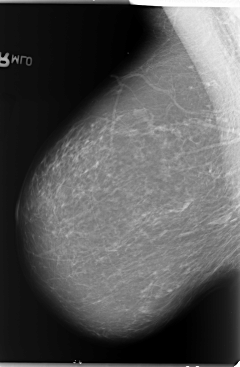

B_3105_1.RIGHT_MLO

LEFT_MLO LINES 5840 PIXELS_PER_LINE 4136 BITS_PER_PIXEL 12 RESOLUTION 50 OVERLAY

FILE: B_3105_1.LEFT_MLO.OVERLAY

TOTAL_ABNORMALITIES 1

ABNORMALITY 1

LESION_TYPE CALCIFICATION TYPE AMORPHOUS DISTRIBUTION CLUSTERED

LESION_TYPE MASS SHAPE OVAL MARGINS ILL_DEFINED

ASSESSMENT 4

SUBTLETY 2

PATHOLOGY BENIGN

TOTAL_OUTLINES 1

BOUNDARY